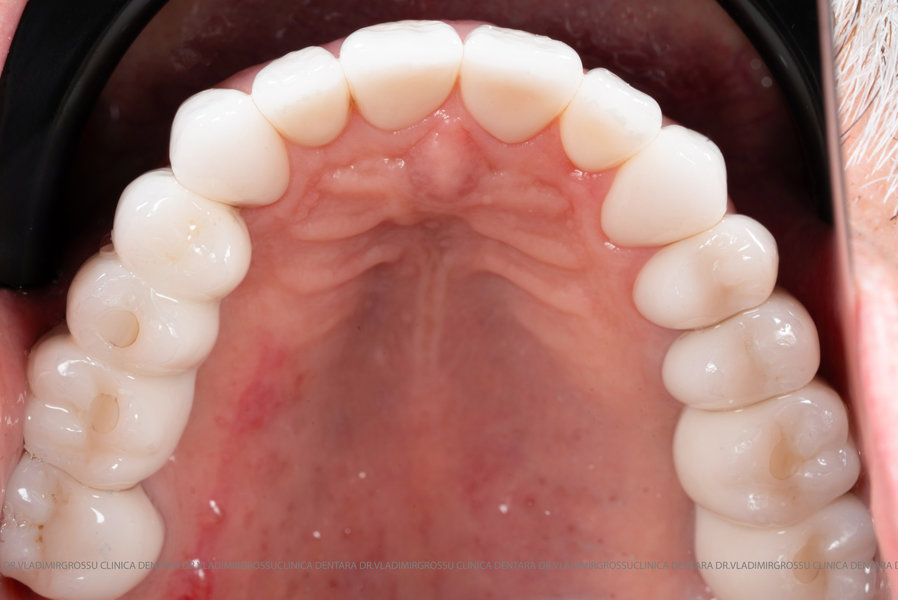

Aditia gingivală este o procedură chirurgicală ce corectează diverse probleme estetice și funcționale, cum ar fi recesiunea gingivală. În implantologia modernă, aditia de țesut moale este utilizată aproape în fiecare intervenție de inserție a implantului dentar pentru a asigura un aspect estetic natural și o bună integrare a implantului în cavitatea bucală.

Adiția osoasă are un rol crucial pentru poziționarea corectă și stabilă a implanturilor dentare. Clinica stomatologică Dr. Grossu din Chișinău promovează o abordare chirurgicală estetică și predictibilă, adaptată fiecărui caz în parte.

Medicii noștri au o vastă experiență atât în chirurgia estetică, cât și în protezarea cu un grad înalt de naturalitate, ceea ce ne permite să gestionăm cu succes și cele mai complexe cazuri.